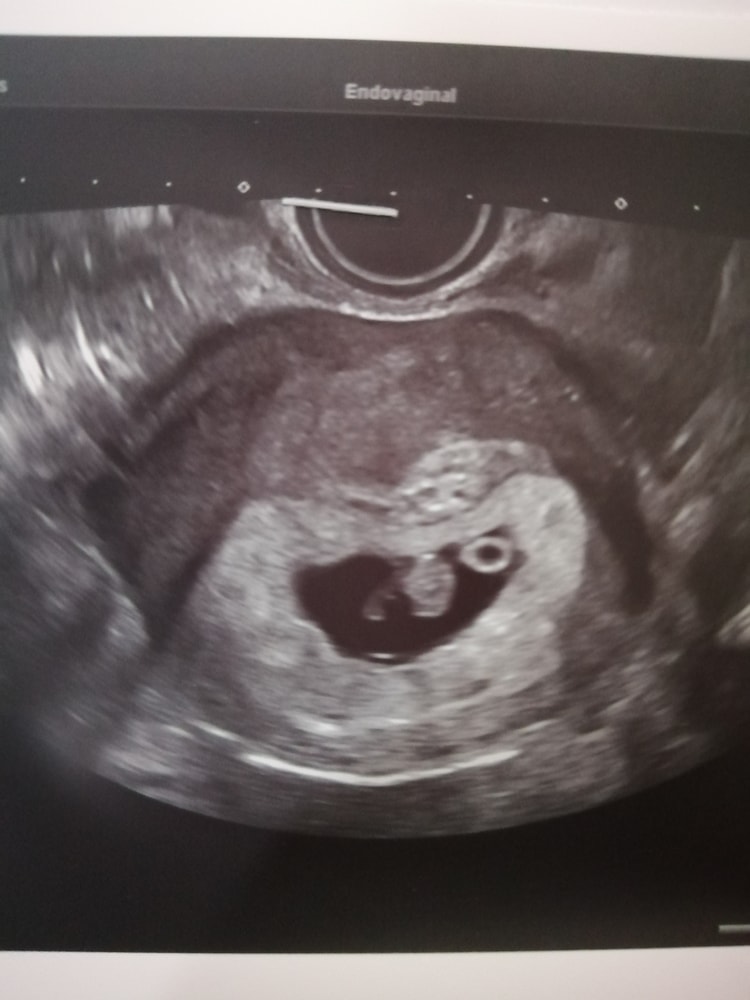

Первое УЗИ ❤️

А что значит ктр маловат? Я так понимаю срок ваш 8 недель,а не 9,ну а пя может и на 10 недель быть, особенно когда хгч растет быстро,плохо когда оно впритык к эмбриону,ну а эмбрион соответственно растет по сроку и срок ставят по его размеру и редко когда бывает чтоб пя и эмбрион одному сроку соответствовали,обычно пя больше срока и это хорошо

Все у вас хорошо У меня на сроке 7+2 Ктр 7мм Свд 28 мм

У меня узи было в 8,1 неделю. Ктр было 15,1мм, свд 35,5мм, жм 5,2мм, чсс 150,срок по узи поставили 7,6 недель. На 1 скрининге срок опережал на 1 день.

Есть нормы только относительно маленького размера СВД. У вас отличная разница, всё в порядке. Посмотрела у себя, у меня было СВД 28,7 мм при КТР 9,8 мм.

Мне даже в 12 недель хороший узист говорила, что ктр замерить правильно до миллиметра нереально Эмбрион то шевелится, где то дальше точку поставили, где то ближе и все, уже +-2 мм в измерениях Все у вас хорошо